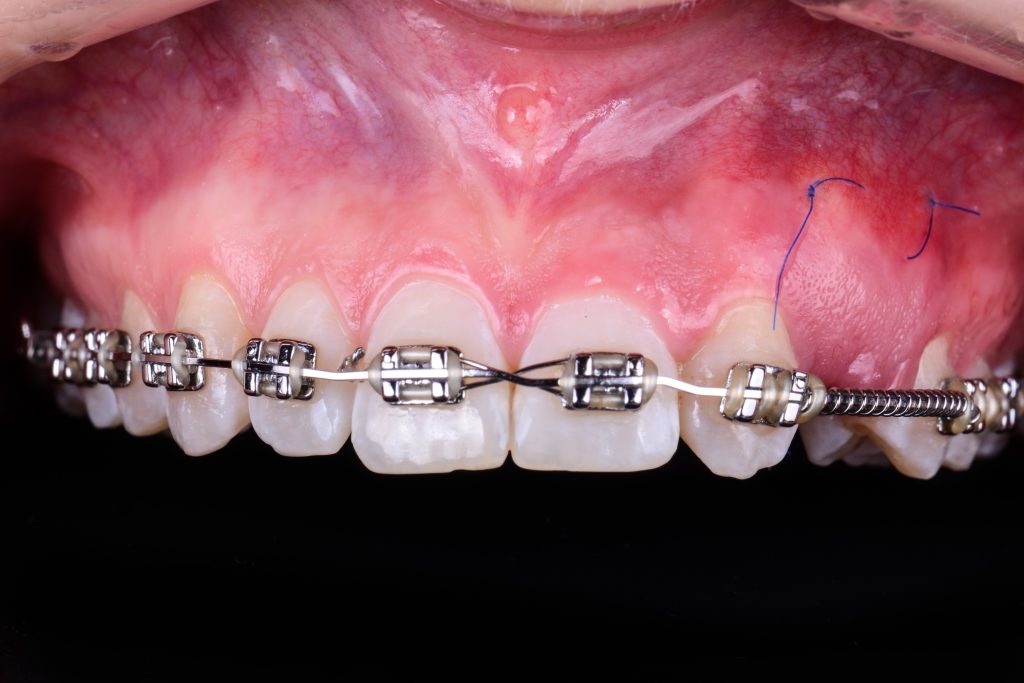

the situation 10 days after the surgery

visible enlarged volume in the gap after connective tissue grafting